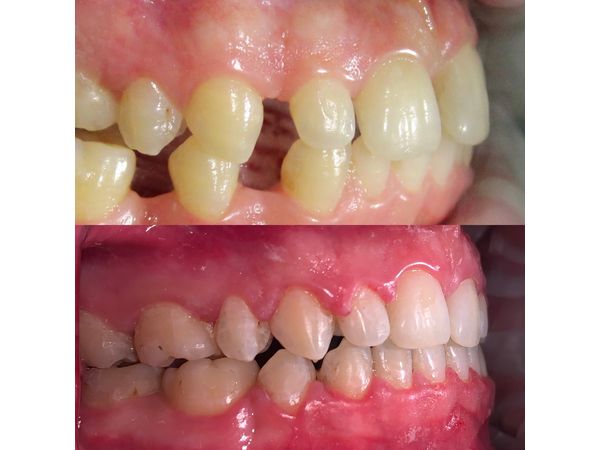

Трансверзальная резцовая окклюзия (смещение средней линии зубов вправо). Аномалия положения зубов. Вторичная адентия (потеря 25 и 35-го зубов).

Пациенту провели санацию полости рта. Чтобы выравнять положение зубов, ему установили самолигирующую брекет-систему Damon Q, в которой ортодонтическая дуга фиксируется с помощью специальных замков. Полнопазная дуга 19×25 из высококачественной нержавеющей стали закрыла щель в области отсутствующих зубов.

В итоге мужчине выравняли зубы, создали правильную форму зубных дуг, закрыли все щели и добились того, чтобы верхние и нижние зубы находились в нормальном положении относительно друг друга.